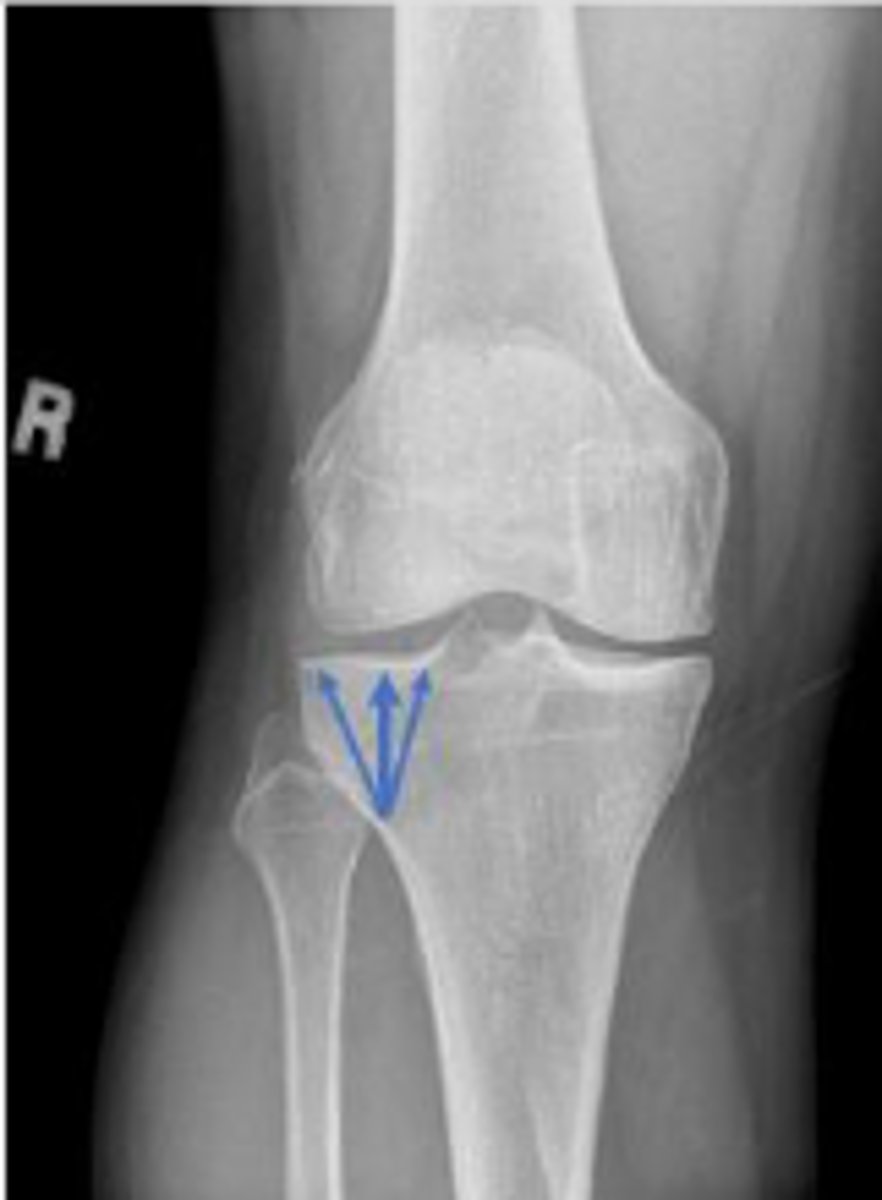

Right proximal tibiofibular joint space

What space are the arrows pointing to?